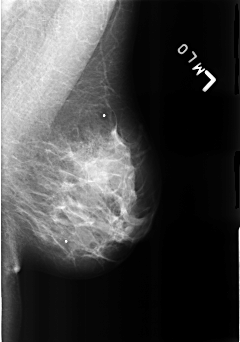

B_3169_1.LEFT_MLO

LEFT_MLO LINES 4440 PIXELS_PER_LINE 3120 BITS_PER_PIXEL 12 RESOLUTION 50 NON_OVERLAY